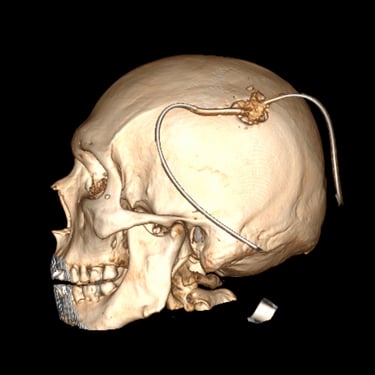

Hematoma subdural subagudo: evacuación mediante burr hole ampliado

El hematoma subdural subagudo se caracteriza por la acumulación progresiva de sangre entre la duramadre y la superficie cerebral, generalmente posterior a un traumatismo craneal. Esta condición puede generar síntomas como dolor de cabeza persistente, confusión, debilidad en extremidades o alteración del estado de conciencia. El tratamiento quirúrgico consiste en la evacuación del hematoma mediante burr hole ampliado, técnica que permite realizar un orificio en el cráneo para drenar el contenido hemático y descomprimir el cerebro. Este procedimiento ayuda a disminuir la presión intracraneal, mejorar los síntomas neurológicos y prevenir complicaciones asociadas a la compresión cerebral.